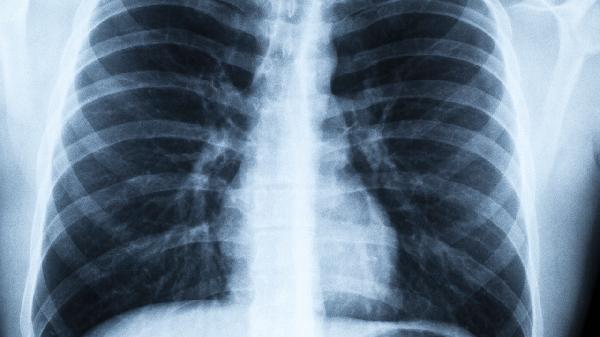

5、定期检查不能少

每年做一次肺功能检查,重点关注FEV1(第一秒用力呼气量)指标。40岁以上人群建议每两年做一次低剂量螺旋CT筛查。